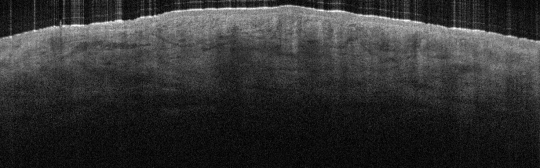

VA1: Right Forearm, Normal